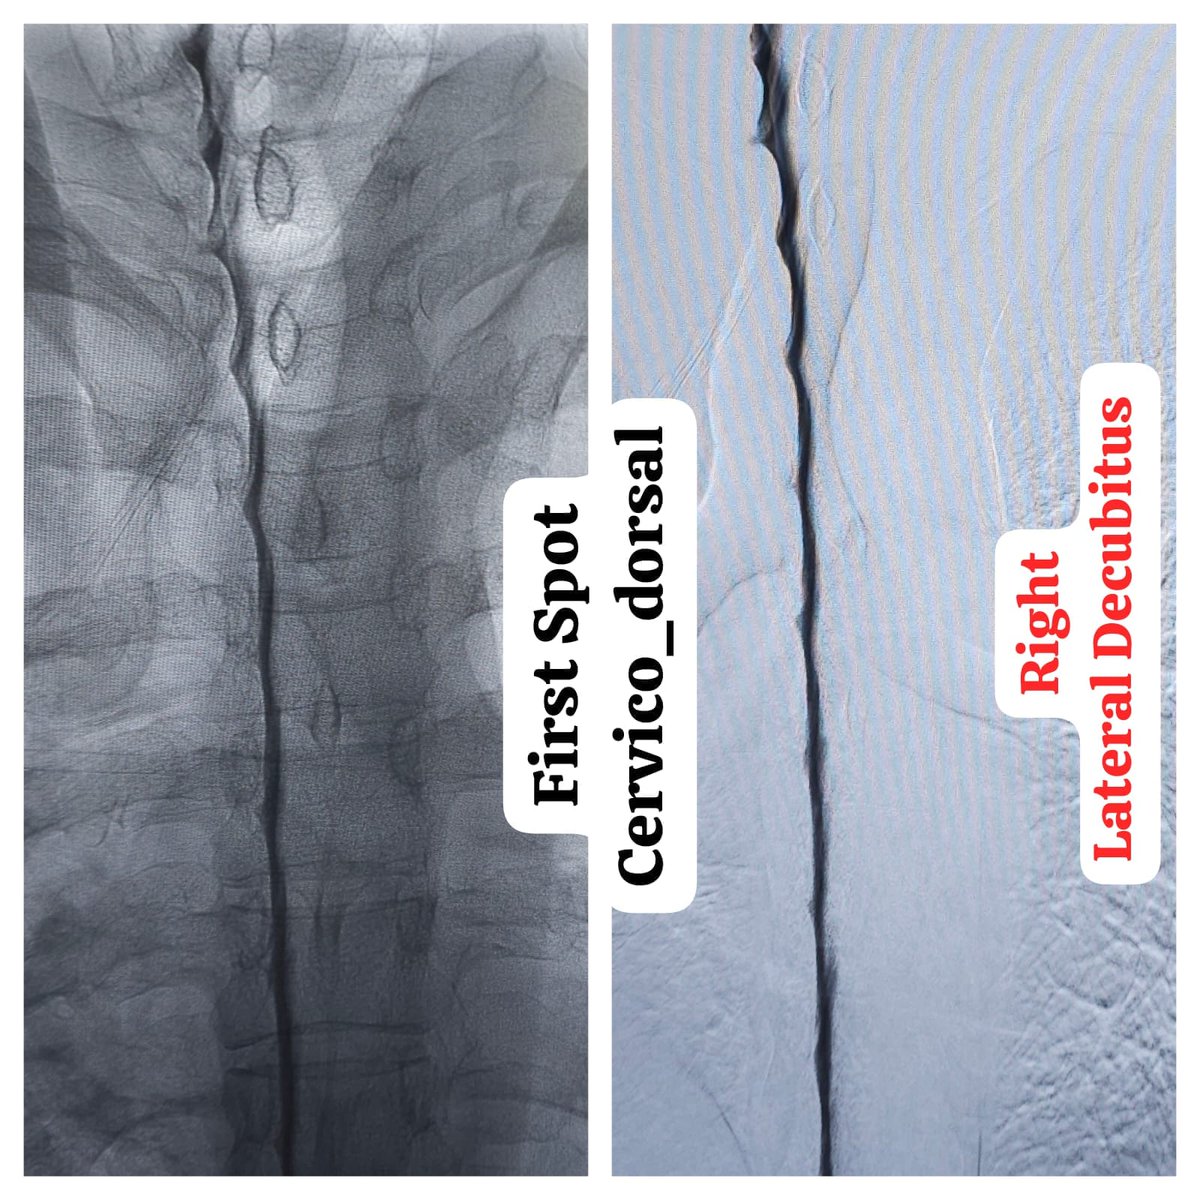

One of the very few centers in the country to offer Digital subtraction Myelography (DSM) @ApolloKarnataka for the Spinal CSF leak patients by our team @SavithKumarINR good news to our patients in India @SpinalCSFCanada @spinalCSFleak @CsfLeakIreland @csfleakinfo #SpinalCsfLeak

SharathKumarGG7's tweet image. One of the very few centers in the country to offer Digital subtraction Myelography (DSM) @ApolloKarnataka for the Spinal CSF leak patients by our team @SavithKumarINR good news to our patients in India @SpinalCSFCanada @spinalCSFleak @CsfLeakIreland @csfleakinfo #SpinalCsfLeak